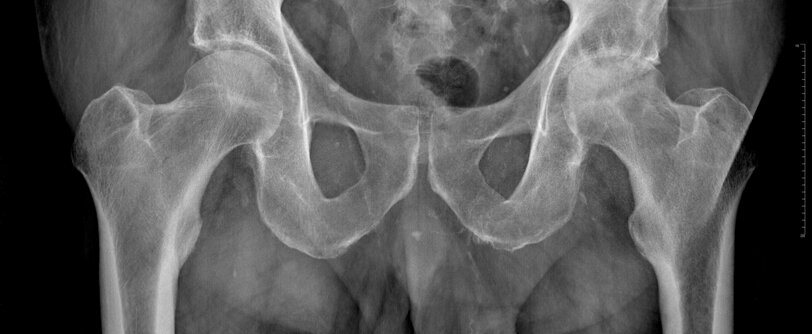

DIAGNOSI

Clinicamente il paziente presenta frequentemente dolore in sede inguinale, che aumenta con i movimenti dell'anca. In condizioni di fratture particolarmente composte (ingranate) il quadro clinico è paucisintomatico con il paziente che può addirittura deambulare. Nella maggior parte dei casi l'arto appare extra-ruotato ed accorciato rispetto al controlaterale (condizione che può venir meno nelle fratture mediali).

L'indagine diagnostica principale per poter eseguire la diagnosi è la radiografia dell'anca, ma in alcuni casi, soprattutto nei casi di frattura ingranata, può esser necessaria l'esecuzione di una TC. Raramente la RM è utilizzata per la diagnosi.